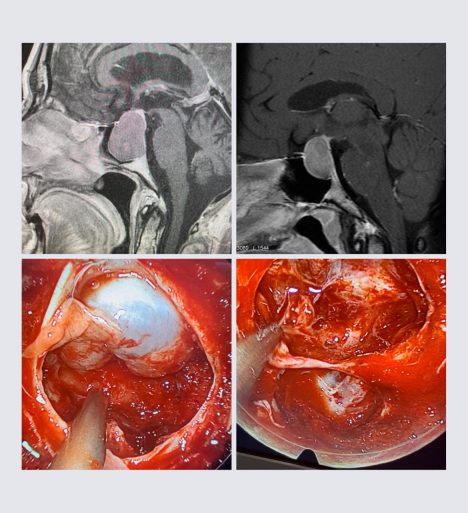

Στην ανωτέρω εικόνα απεικονίζονται δύο διαφορετικά αδενώματα υπόφυσης με το ίδιο αποτέλεσμα: την ολική αφαίρεση του όγκου. Εφαρμόστηκε η διαρρινική ενδοσκοπική προσπέλαση. Σύγκλειση με αιματούμενο κρημνό τύπου Hadat (προσωπικό αρχείο νευροχειρουργού Π. Σταυρινού).